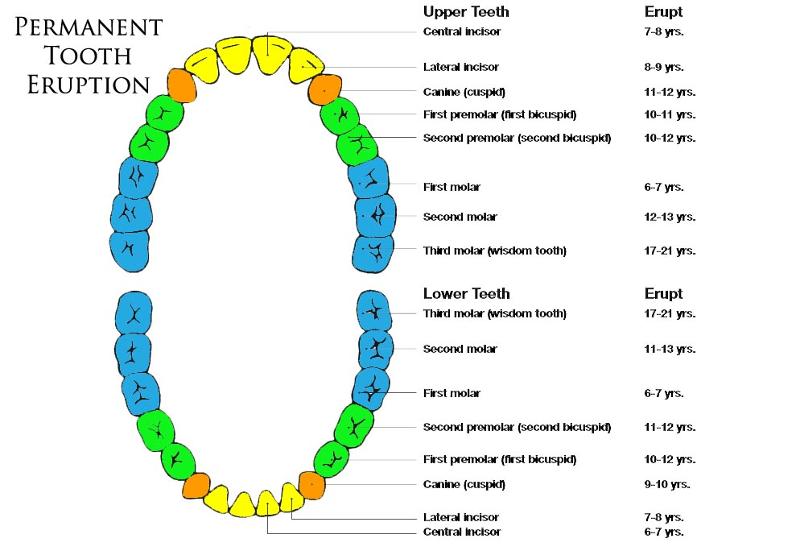

Deciduous Teeth

baby teeth

14

Permanent Teeth

Incisors (8)

Permanent Teeth FRONT

16

Canines (4)

Permanent Teeth

17

Premolars (8)

Permanent Teeth

18

Molars (12)

Permanent Teeth